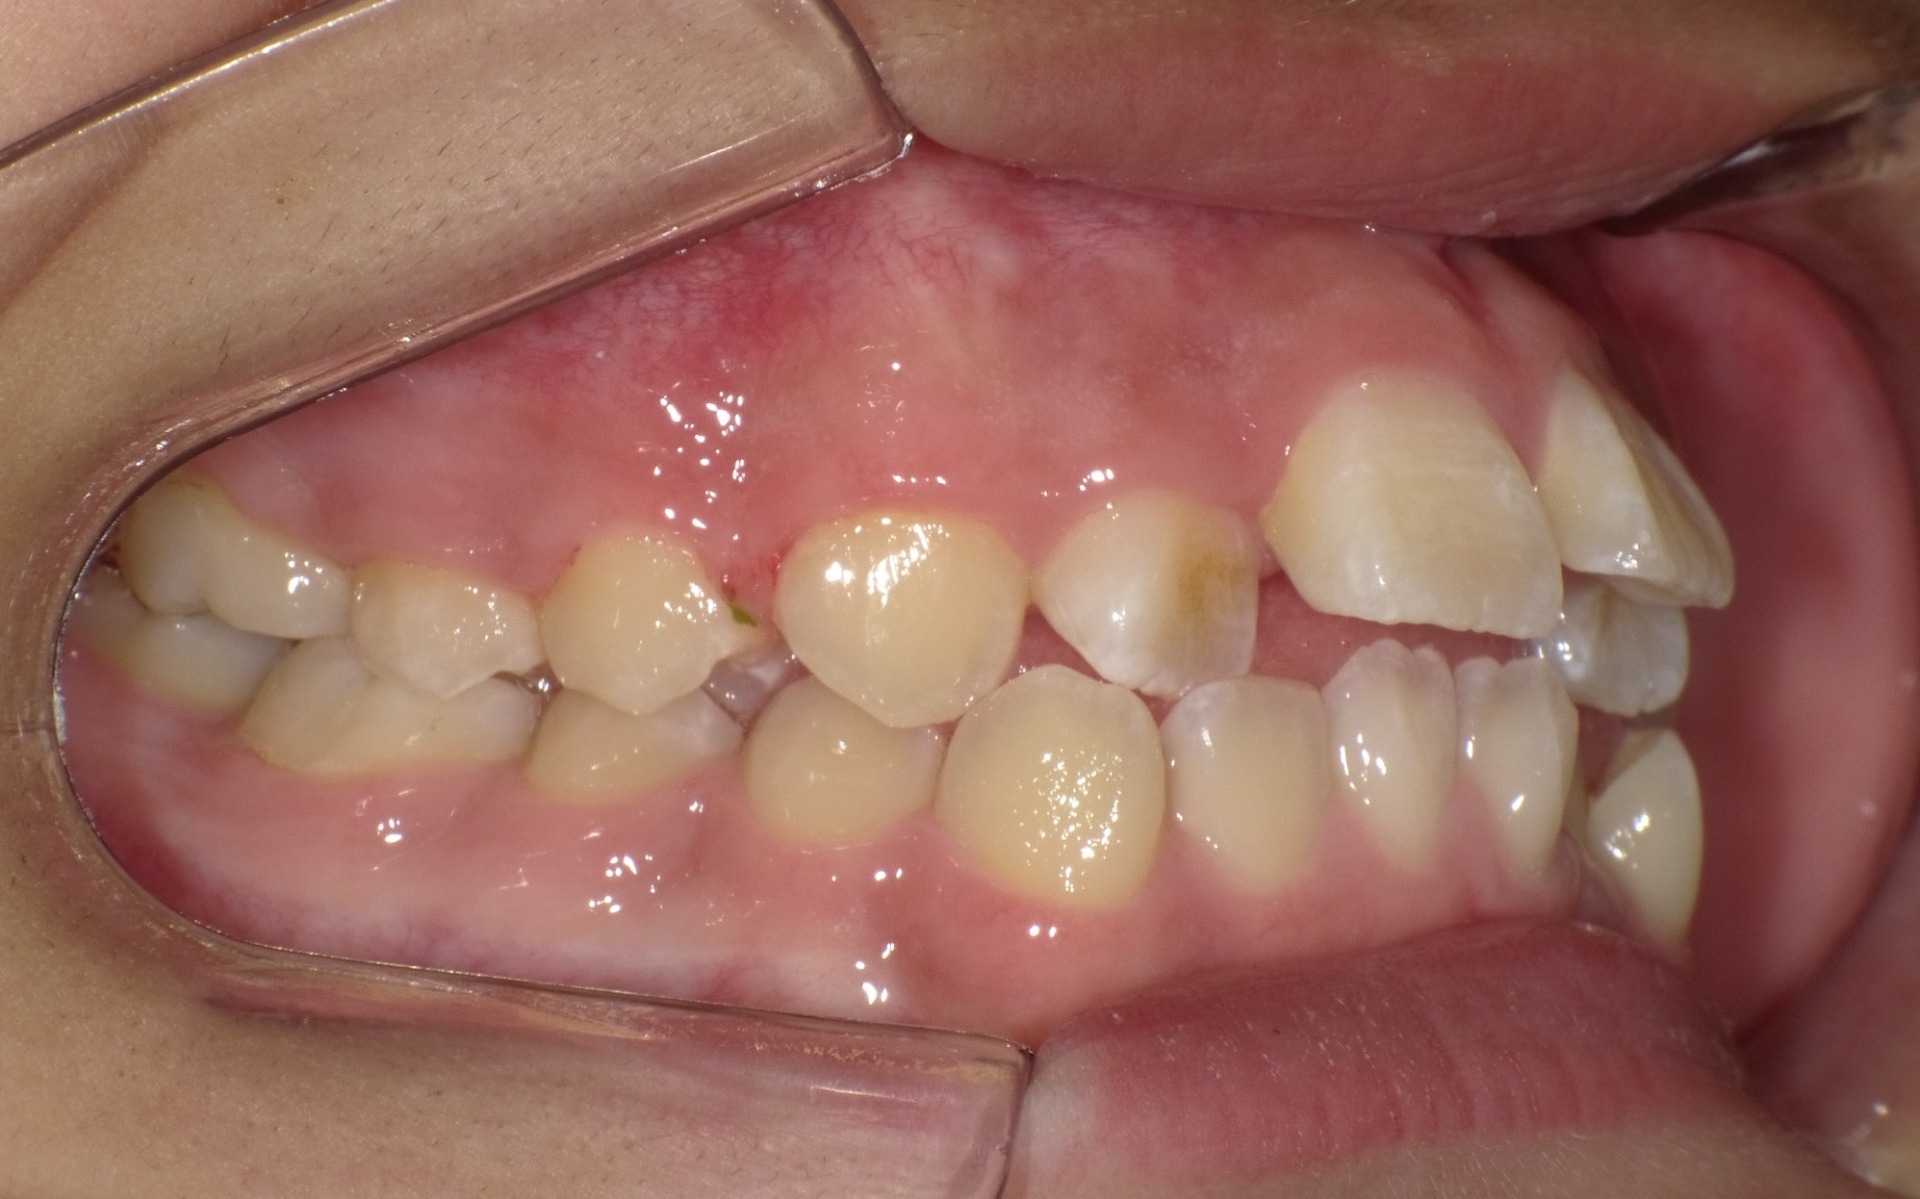

途中経過